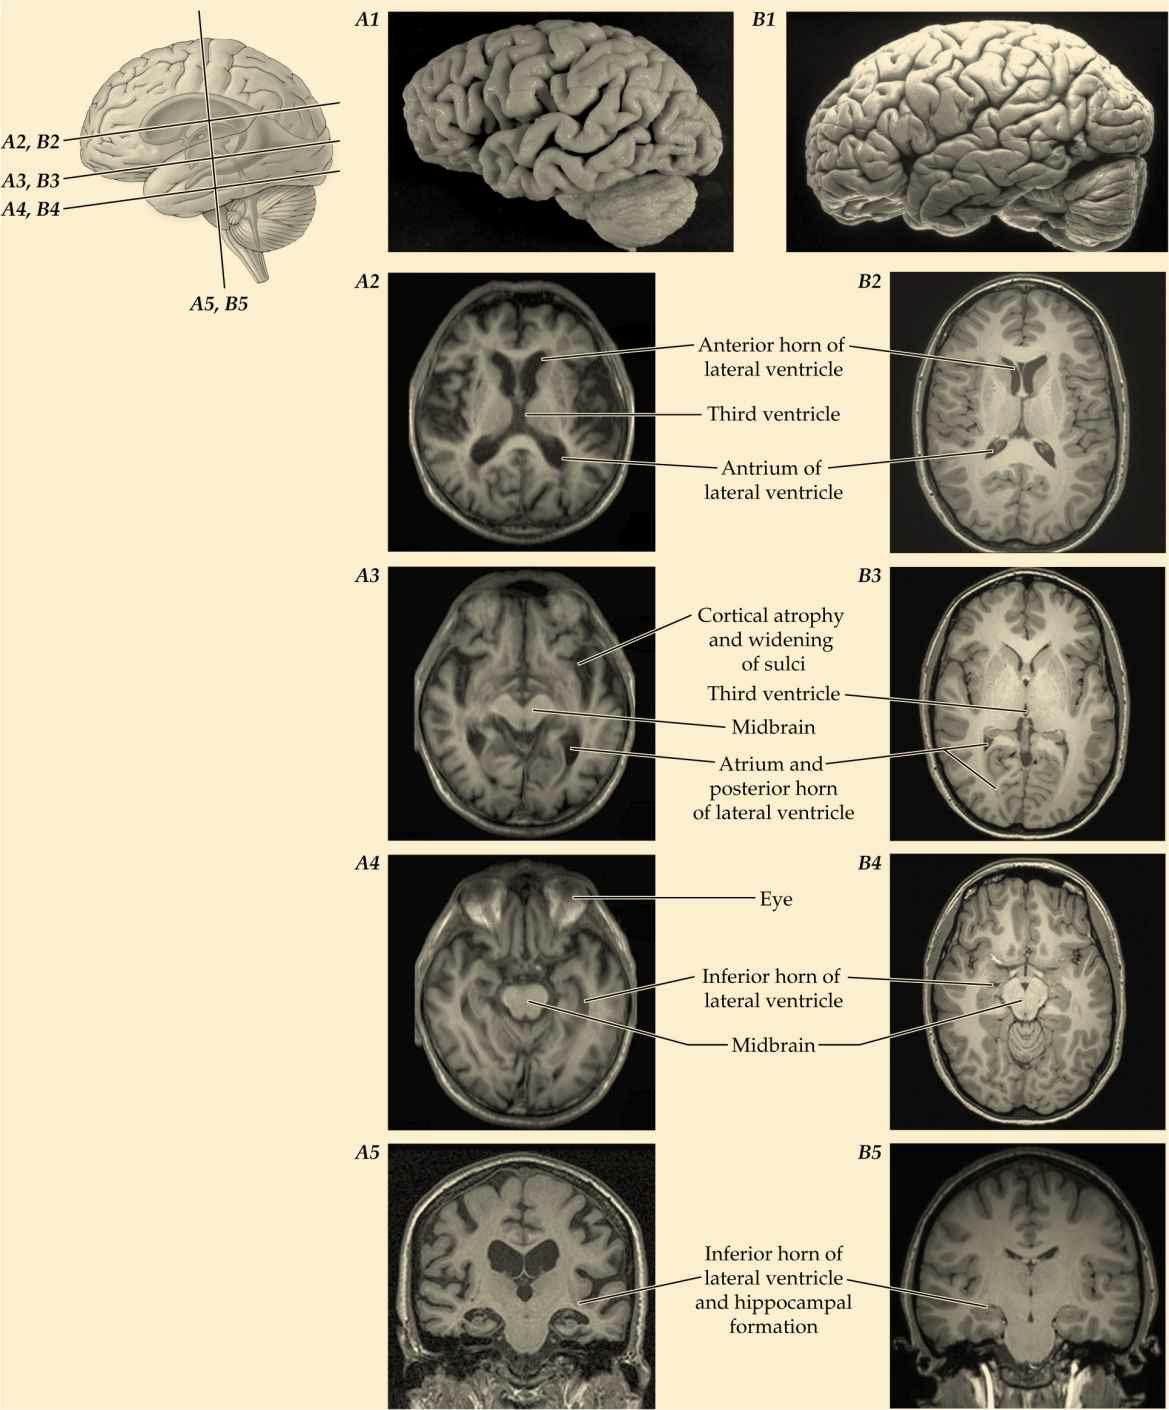

AtlasI:SurfaceTopographyoftheCentralNervousSystem

AtlasII:Myelin-StainedSectionsThroughtheCentralNervousSystem